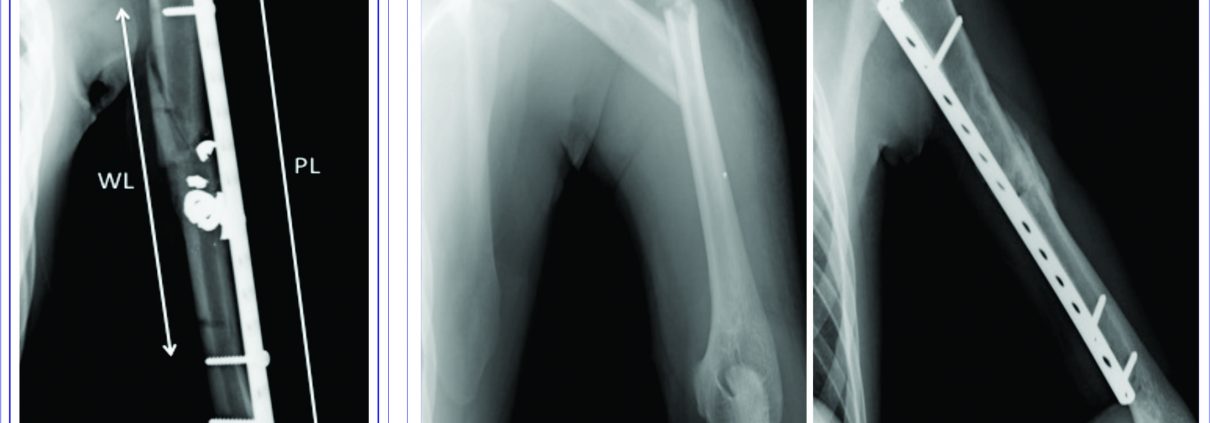

A total of 35 surgeries were performed that met the inclusion criteria during the period from January 2014 to January 2016. Four patients were excluded, three due to death and the other for refusing to participate in the study, totaling a sample of 31 patients, of whom 24 were male (77.4%) and seven female. The mean patient age was 35.3 ± 14.3 years, ranging from 20 to 78 years. We prospectively evaluated the clinical-functional results with a minimum follow-up of six-months, with clinical and radiographic exam data, with EVA[32], DASH[24] functional assessment score, and the SF-12[7] quality of life questionnaire. The DASH results were divided into two groups: satisfactory and unsatisfactory, following the criteria of Chaitanya and Naveen[9]. Medical records data were collected about neurological function before the surgery and after the procedure, the presence of signs of infection of the surgical site, status of the fracture consolidation at six months postoperative, and other associated clinical events. Fractures were classified according to the AO[15] criteria and subsequently divided into simple (type A) and complex (type B and C), with postoperative radiographs being evaluated according to the following parameters: quality of reduction (angular deformity and distance between the main fragments), plate size used, number of screws on each side of the fixation, and working length area of the plate (distance between the screws closest to the fracture site) (Figure 1). Additionally, current radiographs of the humerus in coronal and sagittal views were obtained and were also evaluated regarding the status of consolidation, presence of loosening or failure of the implant, and residual deformity.

Of the 31 participating patients, the mean follow-up time was 19.3 ± 6.1 months. All were right-handed (n = 29; 93.5%), except two. The fracture occurred in the left humerus, in 17 patients (54.8%), and the right humerus, in 14 patients (45.2%). The mean elapsed time until surgery was 6.4 ± 7.0 days, ranging from 0 to 32 days, with a median of five days. The most common cause of the fractures was a car or motorcycle accident (n = 14; 45.2%) and the other causes were: gunshot (n = 7; 22.6%), simple fall (n = 6; 19.4%), and fall from a height or direct trauma (n = 4; 12.8%). The fractures were classified as A in 15, B in 12, and C in 4 cases, grouped into simple (n = 15; 48.4%) and complex (n = 16; 51.6%). Fifteen (15) patients (48.4%) had associated lesions, such as: radial nerve apraxia (n=5; 16.1%), other fractures of the same segment (n = 2), and other lesions (n = 8). The mean range of motion (ROM) of the shoulder was 167° of elevation (± 32.88°), 57° (± 32.88°) of lateral rotation, and internal rotation with mean vertebral level T6 (only four patients had no internal rotation to the thoracic level). In the elbow, the mean ROM was 125° (± 21.05°) in flexion and -5° (± 12.36°) in extension. We found, in our sample, a 90.32% healing rate (28 patients) (Figure 2), with mean values of DASH = 19.2 (± 29.6), SF-12 PCS = 47.1 (±8.7), SF-12 MCS = 52.1 (± 10.7), and VAS = 2.0 (± 2.4) (Table 1).